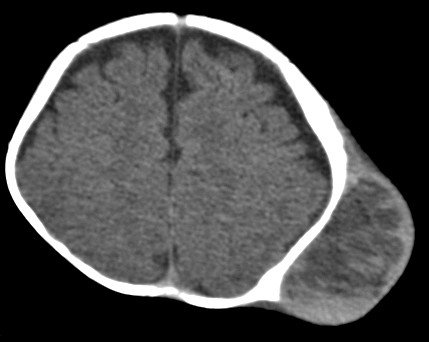

【107-1 醫學(六) 第22題】一位兩歲男孩被帶至門診,媽媽陳述小男孩四天前與其它小朋友嬉戲時,突然有短暫發紺情形但隨即又恢復,這四天來常有陣發性咳嗽及喘鳴,但並無其他鼻塞、流鼻涕等感冒症狀,肺部X光檢查結果正常,下列那一處置是必須優先考慮的?